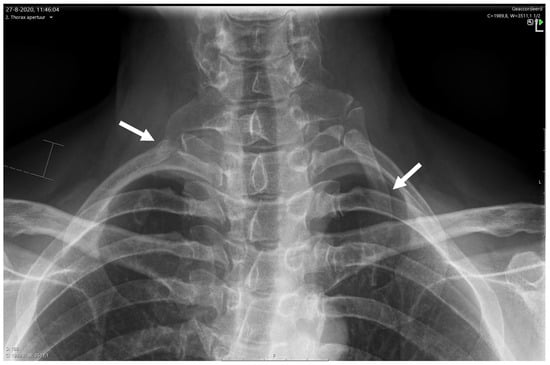

6.3.1. X-ray for NTOS